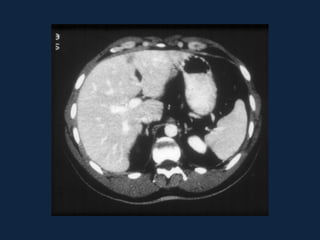

► s/c: Massa esférica, iso ou hipodensa (devido ao conteúdo lipídico).

Hemorragia: áreas hiperatenuantes intra-tumorais, parenquimatosas

ou subcapsulares.

Pode haver gordura ou calcificações.

► c/c:

– Fase Arterial: Realce intenso (< q na HNF) e heterogêneo

– Fase Portal: Diminuição da atenuação e da heterogeneidade do realce.

– Fase Tardia: Isodenso ao parênquima. Realce não persiste.